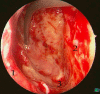

Endonasal endoscopic sinus surgery is the standard procedure for surgery of most paranasal sinus diseases. Appropriate frame conditions provided, the respective procedures are safe and successful. These prerequisites encompass appropriate technical equipment, anatomical oriented surgical technique, proper patient selection, and individually adapted extent of surgery. The range of endonasal sinus operations has dramatically increased during the last 20 years and reaches from partial uncinectomy to pansinus surgery with extended surgery of the frontal (Draf type III), maxillary (grade 3-4, medial maxillectomy, prelacrimal approach) and sphenoid sinus. In addition there are operations outside and beyond the paranasal sinuses. The development of surgical technique is still constantly evolving. This article gives a comprehensive review on the most recent state of the art in endoscopic sinus surgery according to the literature with the following aspects: principles and fundamentals, surgical techniques, indications, outcome, postoperative care, nasal packing and stents, technical equipment.